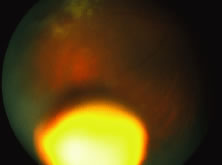

An intraocular sustained-release ganciclovir delivery implant that releases drug into the vitreous is commercially available. The rate of drug release is set at the drug diffusion port to approximately 1μg/hr. The implant is inserted through a sclerotomy at the pars plana and then secured with scleral sutures (Figs. 20 and 21). Studies have shown the median time to progression of CMV retinitis to be about three times longer than with intravenous ganciclovir, or approximately 7 to 8 months.101,102 Thus, replacement of the implant at 7 to 8 months intervals is necessary.103 Serious side effects of implant insertion or exchange are infrequent but include endophthalmitis, retinal detachment, vitreous hemorrhage, and cataract formation.104 Recent reports suggest that there is an increased risk of endophthalmitis in these patients and that such patients may have a poor prognosis for vision. The incidence of endophthalmitis may be as high as 1% to 2%.

Fig. 20. Ganciclovir implant before insertion through the sclerotomy site. Site preparation should include good hemostasis. Care must be taken to insert the implant into the vitreous and not into the subretinal space.

Fig. 21. Colored fundus photo showing the intravitreal ganciclovir implant after insertion. An area of active cytomegalovirus (CMV) retinitis is seen in the upper portion of the illustration.